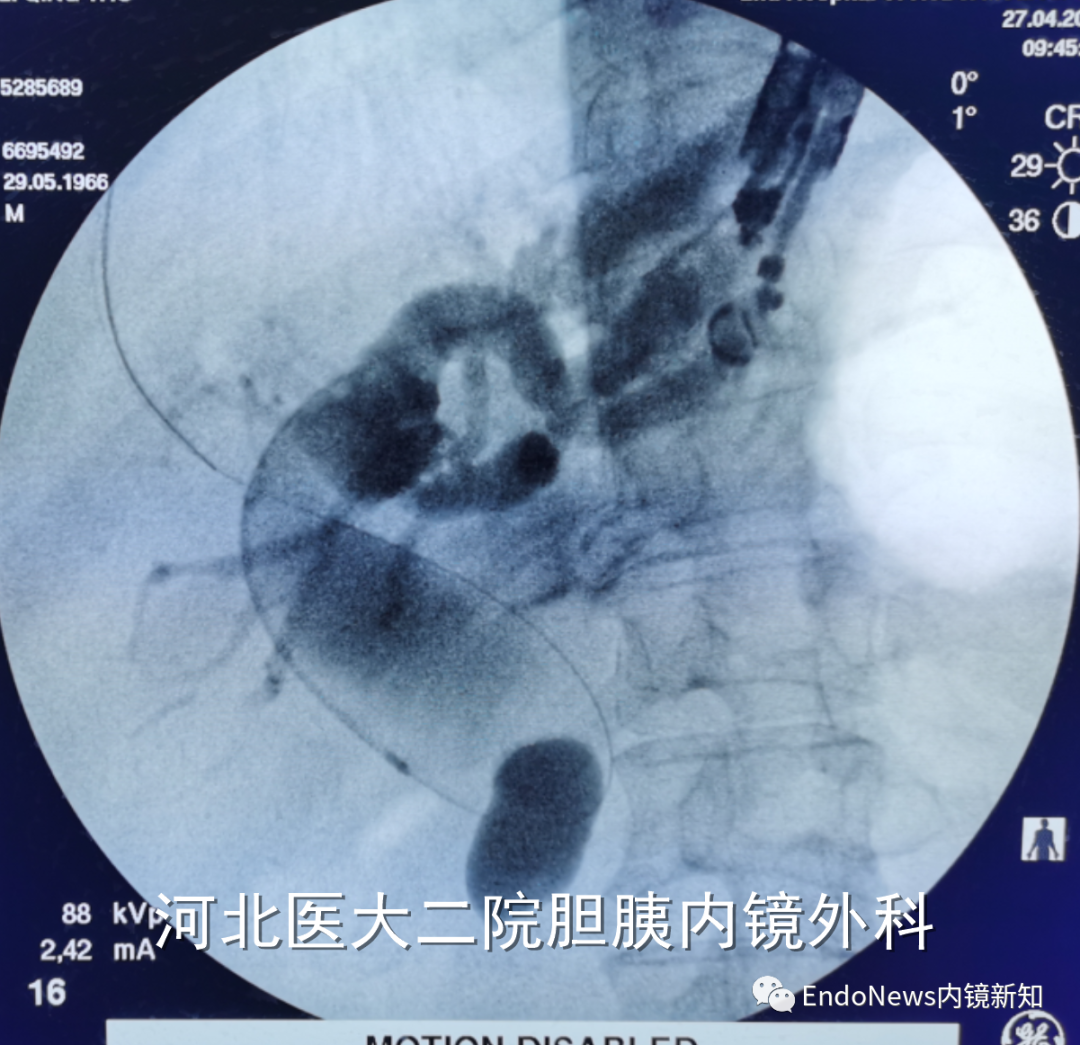

如下图所示,肝门胆管狭窄(Bismuth IV型),导丝进入肝右叶胆管后就可以置入支架引流肝右叶胆管:

取石网篮 为什么贵EUS-BD操作中的细节:导丝如何超选?_https://www.jmylbn.com_新闻资讯_第14张

取石网篮 为什么贵EUS-BD操作中的细节:导丝如何超选?_https://www.jmylbn.com_新闻资讯_第15张

在下面肝内胆管结石的病例所示,这是一个进肝右叶管之后顺行放置双猪尾支架,在二期手术时将窦道扩开,用字母镜液电碎石,再在右侧肝内胆管管进行取石的病例。